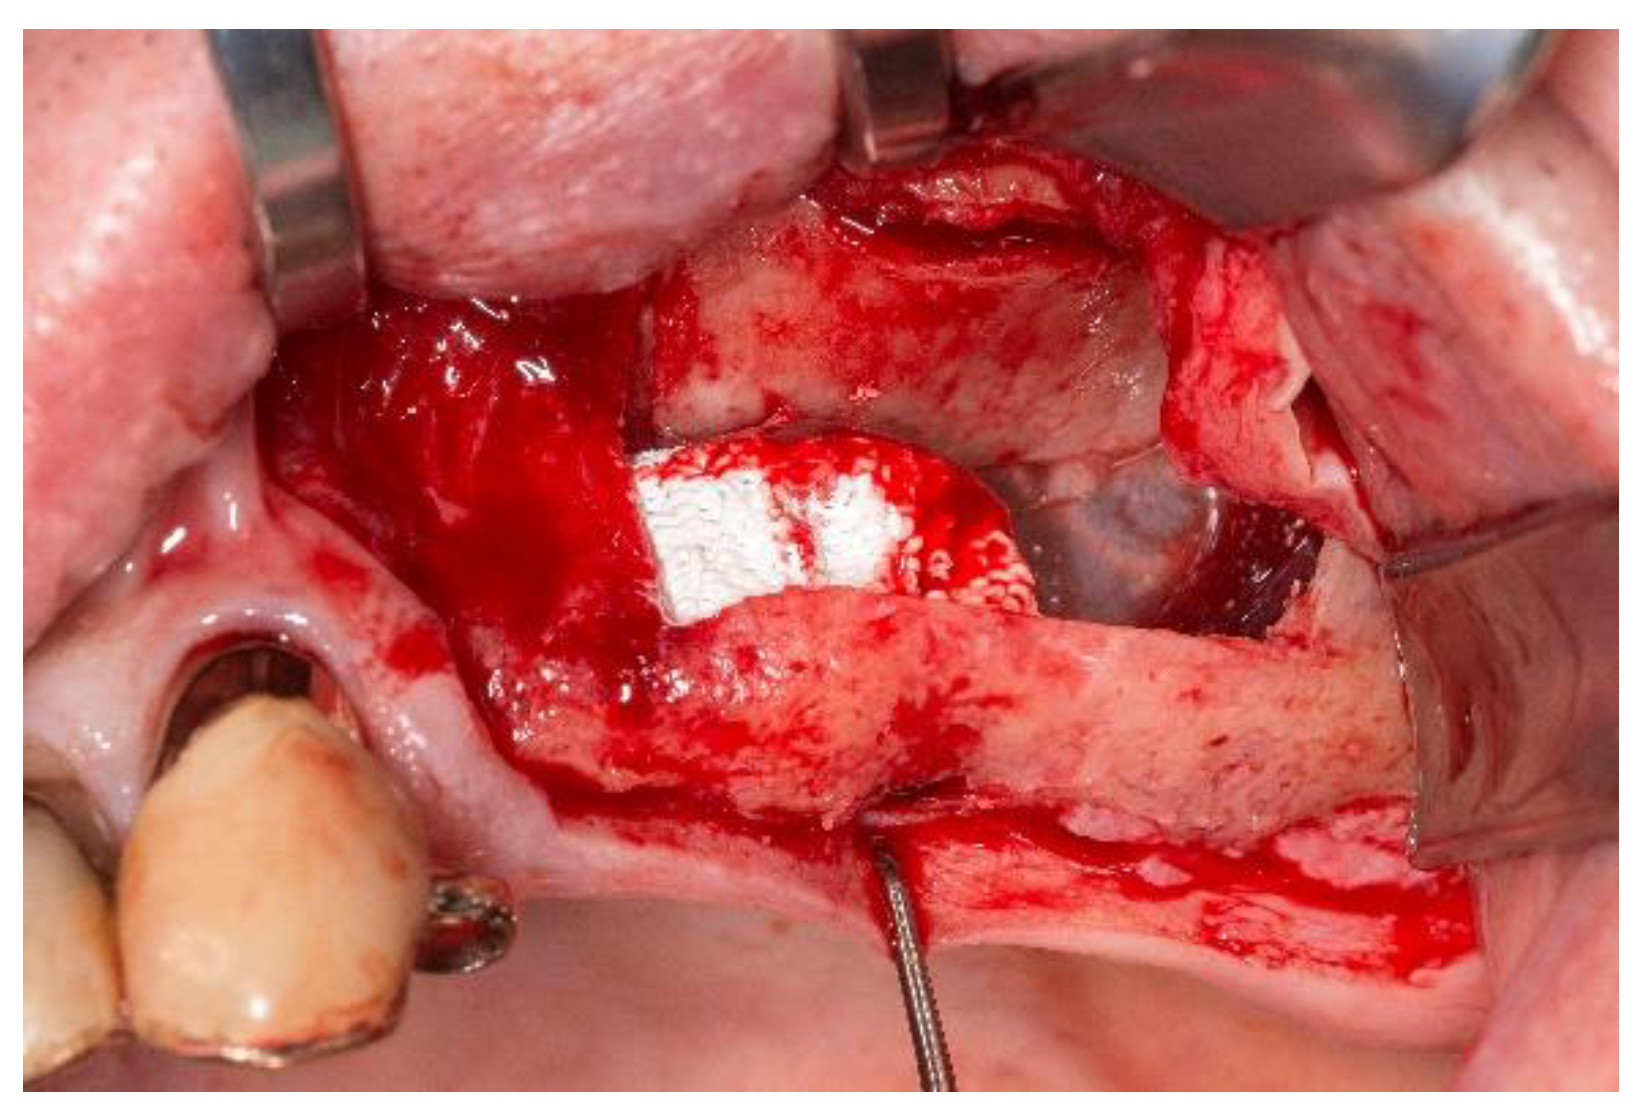

2. Case Presentation

3.1. Handling of the Scaffolds and Clinical Outcome